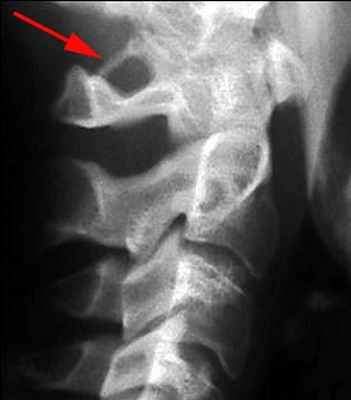

![]() |

| Аномалия Киммерли |

К числу других причин относятся также патологические извитости, врожденные нарушения развития в виде гипо- и аплазии позвоночной артерии, аномалия Киммерли. При наличии последней при повороте головы происходят перегиб и компрессия позвоночной артерии с ее возможной травматизацией.

Особой формой острого нарушения мозгового кровообращения в ВББ является инсульт “лучника” (bowhunter’s stroke), связанный с механической компрессией позвоночной артерии на уровне шейного отдела позвоночника при крайнем повороте головы в сторону.

Механическая компрессия позвоночной артерии на уровне шейного отдела позвоночника,

лежащая в основе развития инсульта “лучника”.

Механизм развития такого инсульта объясняется натяжением артерии при повороте головы, сопровождающимся надрывом интимы сосуда (диссекцией) особенно у больных с патологическими изменениями артерий.